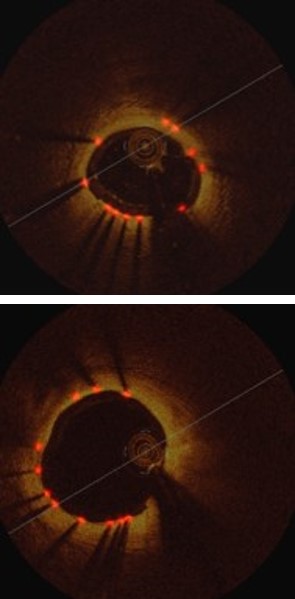

Refer to caption

Figure 3: Strut detection results: (a) Comparison of our method to the existing methods, (b) component analysis of our method.

Table 1 shows the detection results of our method compared to the state-of-the-art methods, where it increases recall by 1.2% and precision by 4.7%, relative to the second best results from Faster-RCNN, as shown in Fig 3(a).

Table 1 and Fig. 3(b) show the detection results of our method at individual stages. Fig. 5(a) shows the two example detection results with various thickness coverage. The Local-Network shows the higher recall while Global-Network achieved better precision results (as shown in Fig. 5(c) and Fig. 5(d)). As exemplified in Fig. 5(e), the proposed method integrated both Local Network and Global-Network and achieved a better consistent performance in recall and precision.